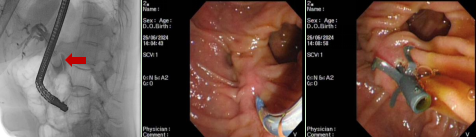

病例2

患者,女,77岁,主因“皮肤黄染、烧心、乏力1个月”入院,既往患高血压、糖尿病、冠心病10余年,曾因“病窦综合征”行起搏器植入术,有胆囊切除病史。腹部增强CT提示:壶腹周围占位继发胆道系统梗阻可能,腹膜后淋巴结转移可能。给予患者内镜下逆行胰胆管造影术并给予胆道金属支架置入。